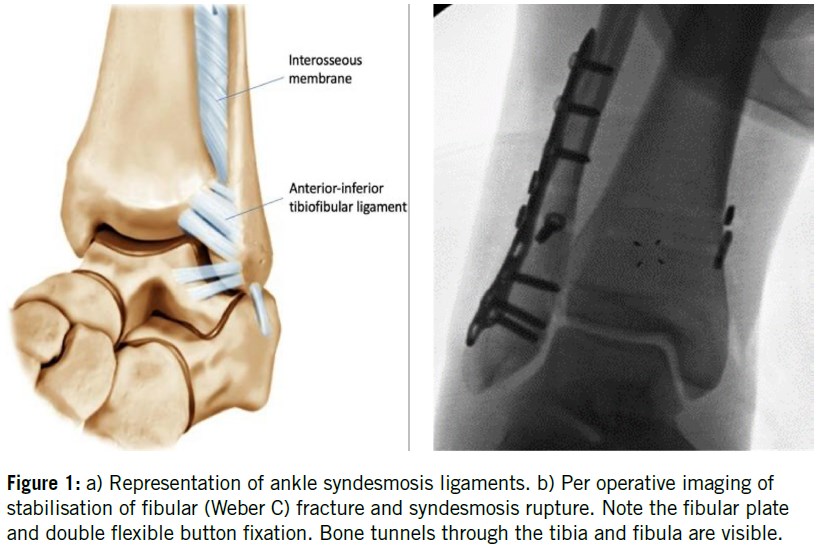

Syndesmotic injuries occur in athletes at an estimated incidence of 0.05 injuries per 1000 hours of exposure1. Specifically, impact and collision sports such as soccer, skiing, football, ice hockey, wrestling, and rugby exhibit a higher incidence of this type of injury1. It is widely recognized that syndesmotic injuries result in 1) substantially longer time loss from sport compared to other ankle ligament injuries, 2) are much more likely to require surgical stabilization (Figure 1), and 3) are associated with more long-term functional sequelae.